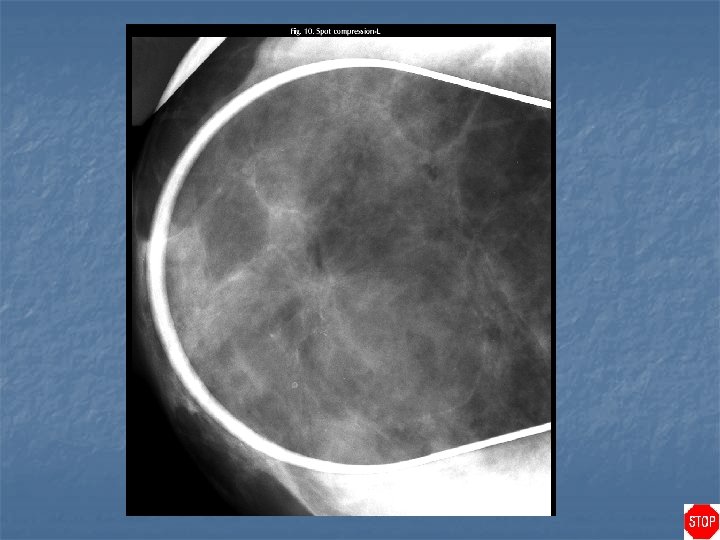

Radial scar n Case findings: n n n 7 mm density in retroareolar location in the left breast, with radiating linear strands surrounding it Best seen on the CC view Spiculated lesion, central nidus with internal radiolucencies ( white star) Predominantly radiolucent spiculations (rather than radiodense) Requires open surgical biopsy malignancy present in 25% of cases (some are invasive carcinomas, but others are radial scars that have small internal or adjacent areas of carcinoma) Open surgical biopsy: less subject to sampling error than are percutaneous biopsy procedures (aspiration or core biopsy)

Case directory Spiculated lesion n Malignant: n n n MC invasive ductal (90%), invasive lobular (10%) Malignant spicules: extend in all directions from a central tumor mass Benign: n n n MC radial scar, sclerosing adenosis Post-surgical scar: change in shape and density on different projections, contain central lucency, and regress over time, follow-up within 6 months Benign spicules: bundled in parallel